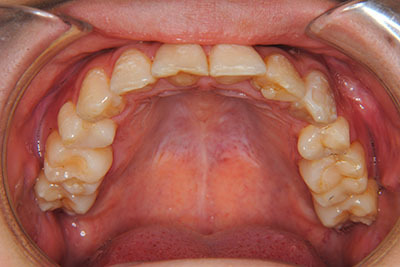

マルチブラケット装置(T21ブラケット)に加えて口の中のゴムをたいへん頑張って使っていただいた結果、治療前の予想期間1年から1年半であったところ、10カ月で動的治療を終了できました。上下真ん中のズレも治りぴったりになりました。 これからは歯並びの維持安定のためリテーナー(保定装置)を使いながら定期健診となります。

⑧リスクと副作用:マルチブラケット装置(T21ブラケット)を初めてつけてから3,4日、食事の時に歯が少し痛かったとのことでした。治療後のエックス線写真で、歯根吸収はほとんど観察されませんでしたが、歯肉を診ると残念ながら下の真ん中の前歯2本の間に若干の歯肉退縮(ブラックトライアングル)が生じていました。